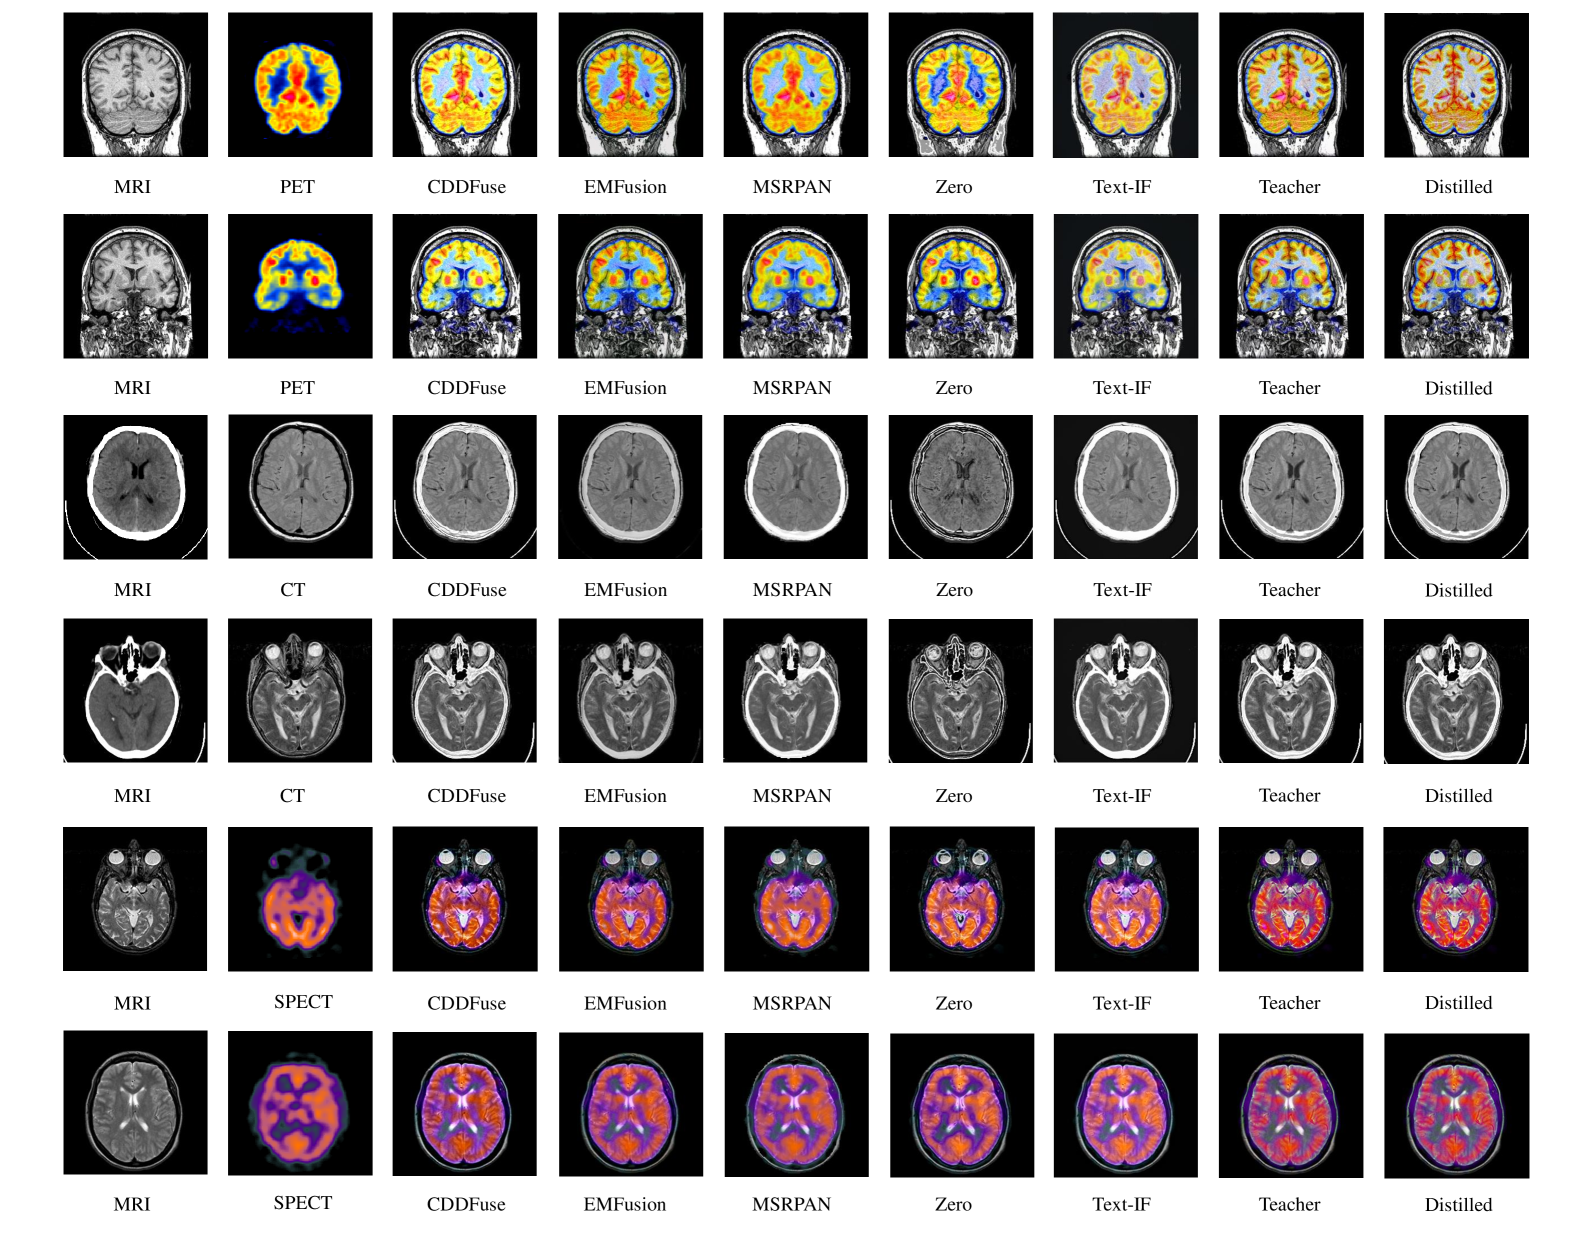

4.3 Comparison on Medical Datasets

To demonstrate the generalization capability of our method, we evaluate its performance on medical image fusion tasks. As shown in Table 2, both our teacher and student networks achieve superior performance across different modality pairs. The improvement is particularly significant in structural preservation metrics (SSIM and QAB/FQ^{AB/F}), which is crucial for medical applications.

Refer to caption

Figure 4: Compare with previous SOTA text-guided image fusion method Text-IF on Havard Medical Image Fusion Datasets. More can be found in appendix.

For SPECT-MRI fusion, our method shows notable advantages in preserving functional information while maintaining anatomical details. In CT-MRI fusion, where structural alignment is critical, our approach achieves the highest SSIM scores, indicating better structural preservation. The PET-MRI results further confirm our method’s effectiveness in handling multi-modal medical images with different characteristics. Figure4 presents visual examples from different medical modalities. Our fusion results exhibit better detail preservation and contrast enhancement, which is essential for clinical applications. The distilled student network maintains these advantages while significantly reducing computational requirements, making it more practical for clinical deployment.

B.2 More Comparison on Medical Images

Table 11 extends our evaluation to medical image fusion tasks across three modality pairs (PET-MRI, CT-MRI, and SPECT-MRI) using additional metrics including SSIM, VIF, QAB/FQ^{AB/F}, MI, and EN. The results demonstrate our method’s strong generalization capability across different medical imaging modalities.

For PET-MRI fusion, our distilled model achieves the highest scores in SSIM (1.243) and VIF (0.929), indicating superior structural preservation and perceptual quality. In CT-MRI fusion, both teacher and student networks maintain high performance, particularly in structural metrics (SSIM: 1.313) and edge preservation (QAB/FQ^{AB/F}: 0.657). The SPECT-MRI results further validate our method’s effectiveness, with the distilled network showing exceptional performance in information preservation (MI: 4.371) while maintaining high structural fidelity.

C.2 Visual Comparison on Medical Images

Figure 9 showcases detailed visual comparisons across different medical imaging modalities. The results highlight our method’s advantages in: 1) Preserving fine anatomical structures from both modalities 2) Maintaining clear tissue boundaries and contrast 3) Effectively combining functional information (PET/SPECT) with anatomical details (MRI) 4) Producing clinically meaningful fusion results with enhanced diagnostic value